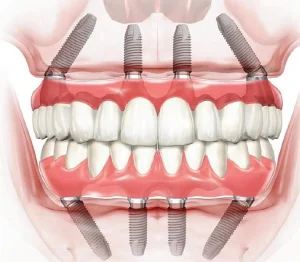

Имплантация All-on-4, All-on-6, All-on-8

Технология All-on-4, All-on-6 и All-on-8 – это революционное решение для полного восстановления зубного ряда.

В зависимости от состояния костной ткани пациента, устанавливаются 4, 6 или 8 имплантов, на которые фиксируется несъемный протез. Этот метод позволяет восстановить улыбку всего за одно посещение клиники, что особенно важно для пациентов с полной адентией (отсутствием зубов).

Цифровое моделирование помогает определить оптимальное расположение имплантов, чтобы обеспечить равномерное распределение нагрузки и высокую прочность конструкции.